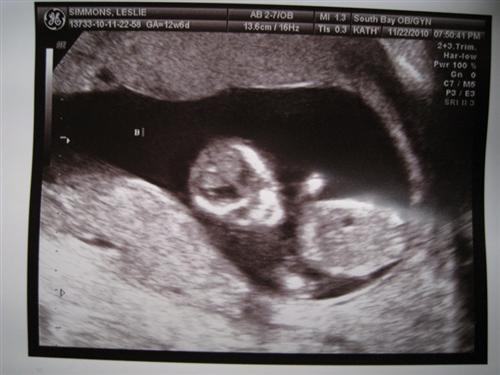

13 weeks with Ultrascreen pics

Baby A was sucking their thumb and Baby B was snuggling Baby A

They definitely share a placenta and there is a very very thin membrane separating them. I have to see the High Risk Dr. in two weeks. So far so good though!